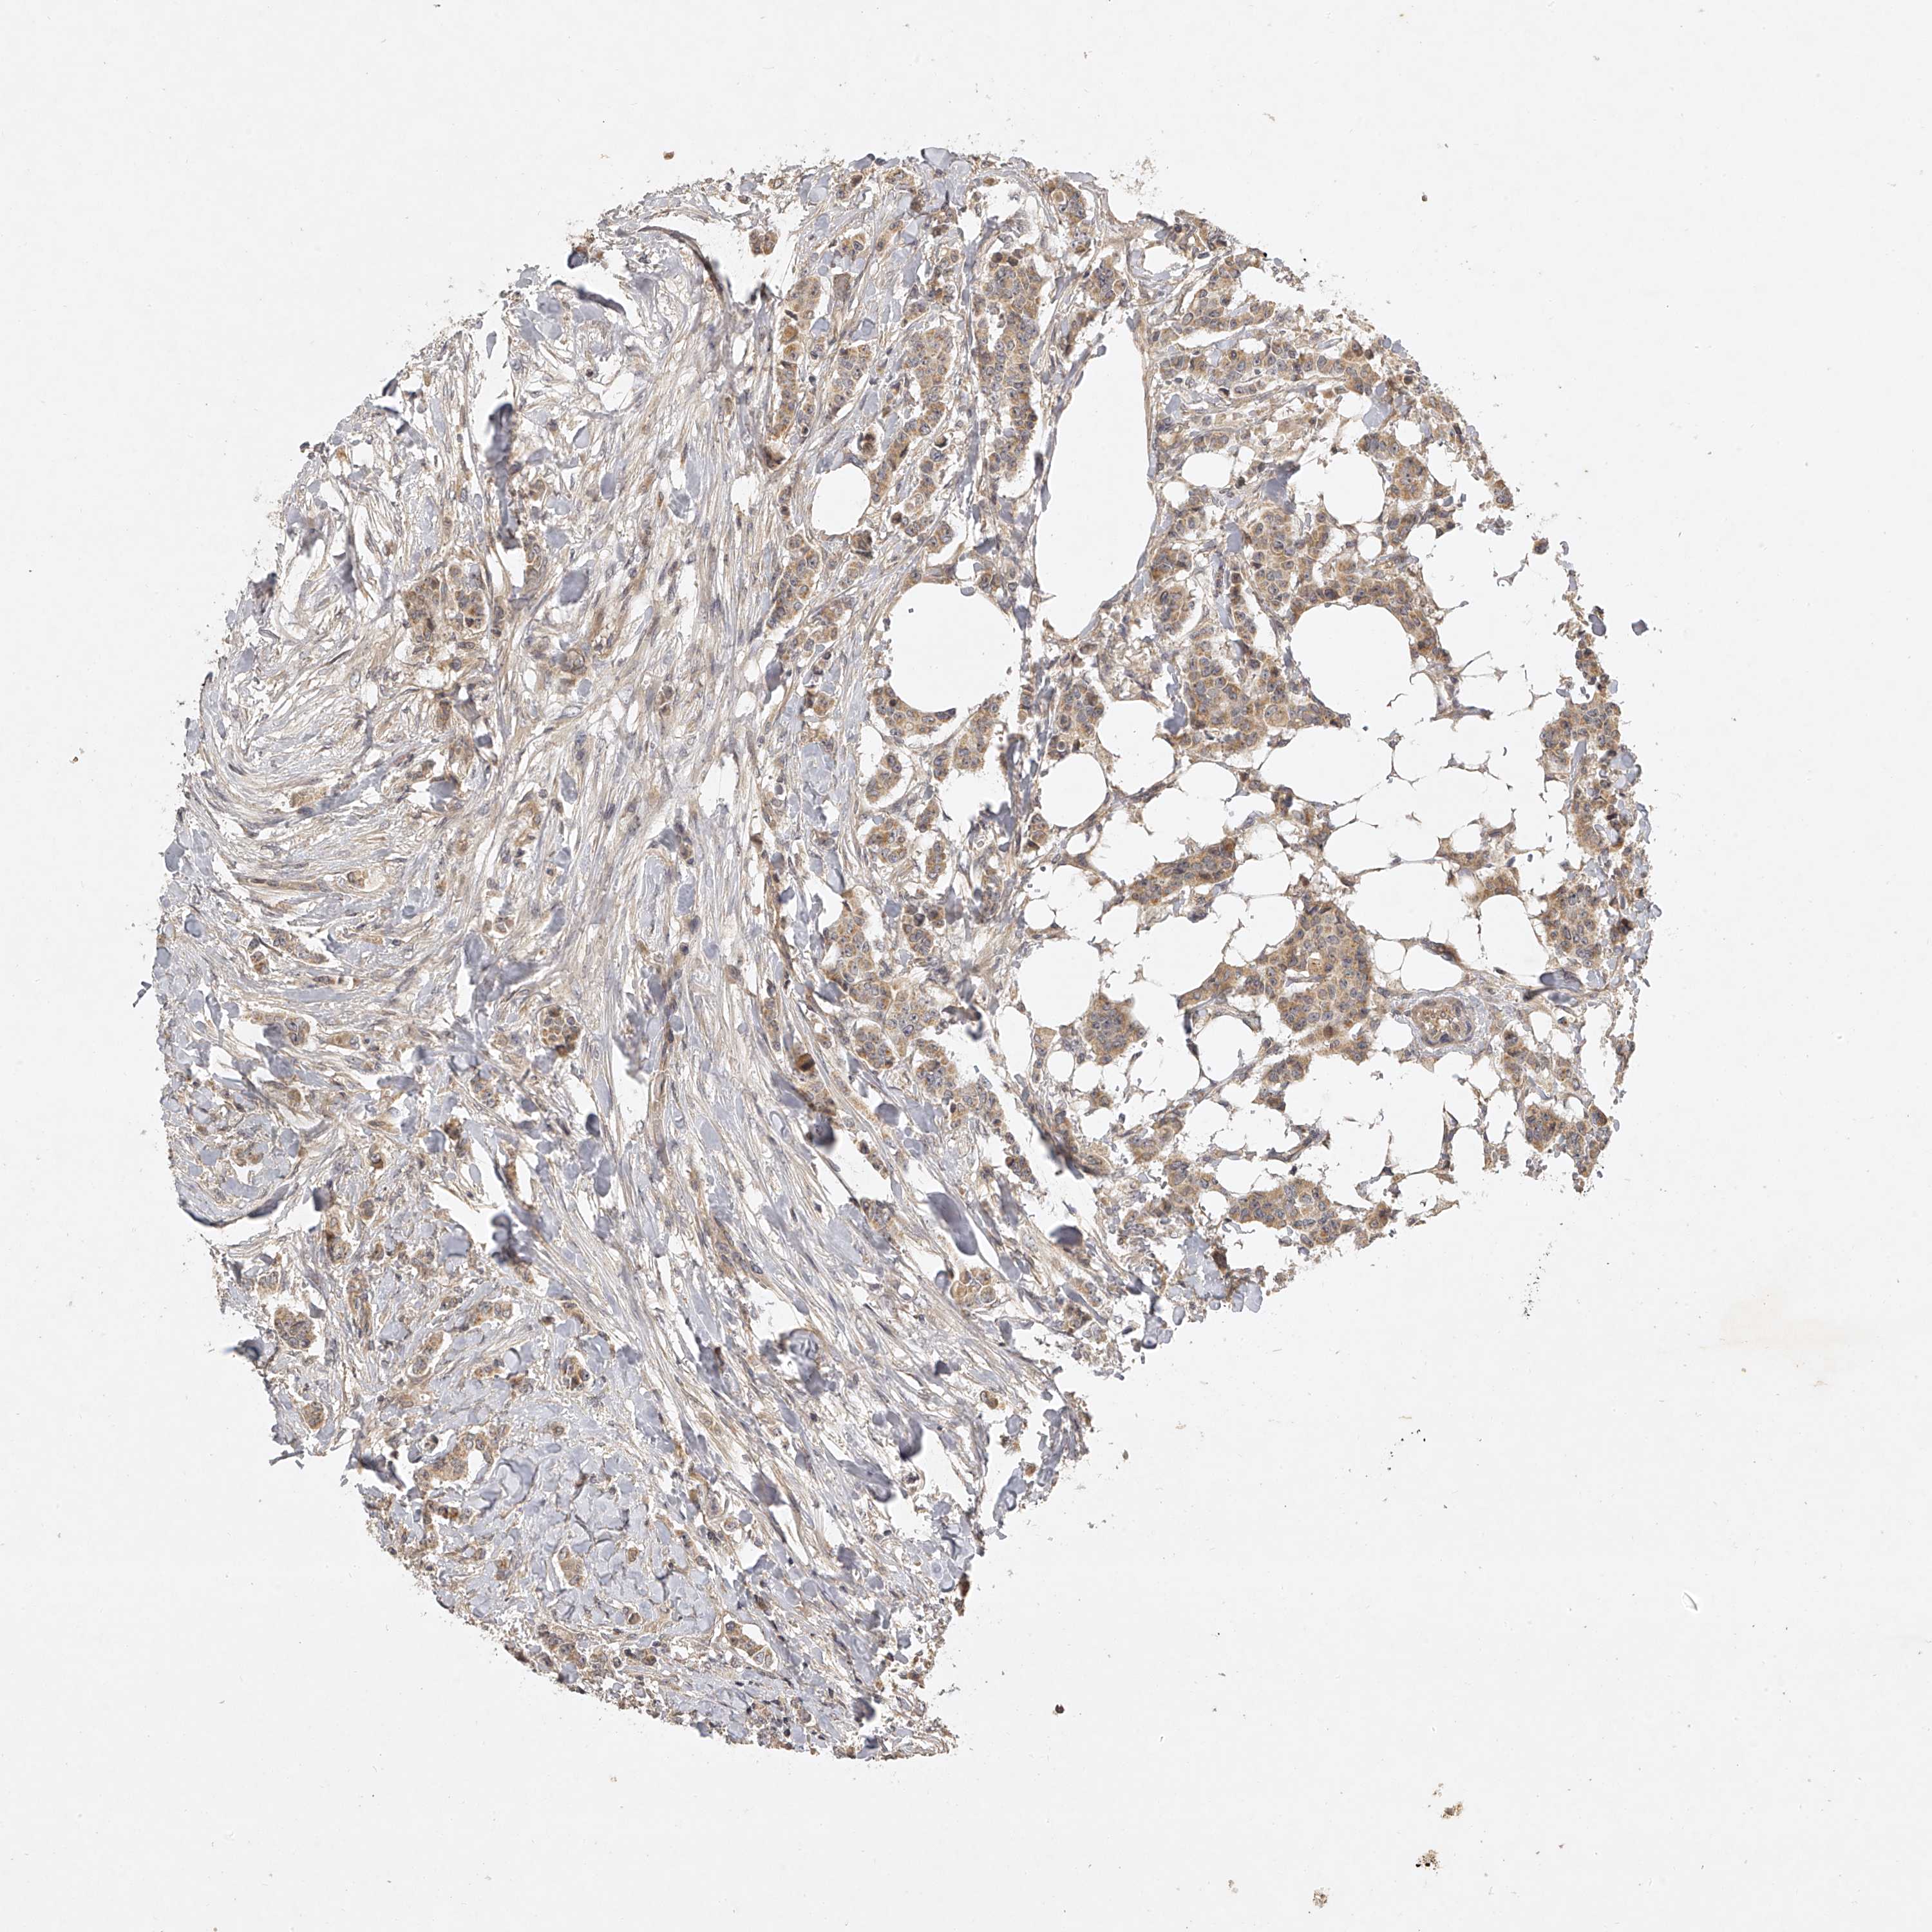

CANCER BREAST CANCER Show tissue menu

BRCA TCGA BRCA VALIDATION PROTEIN EXPRESSION